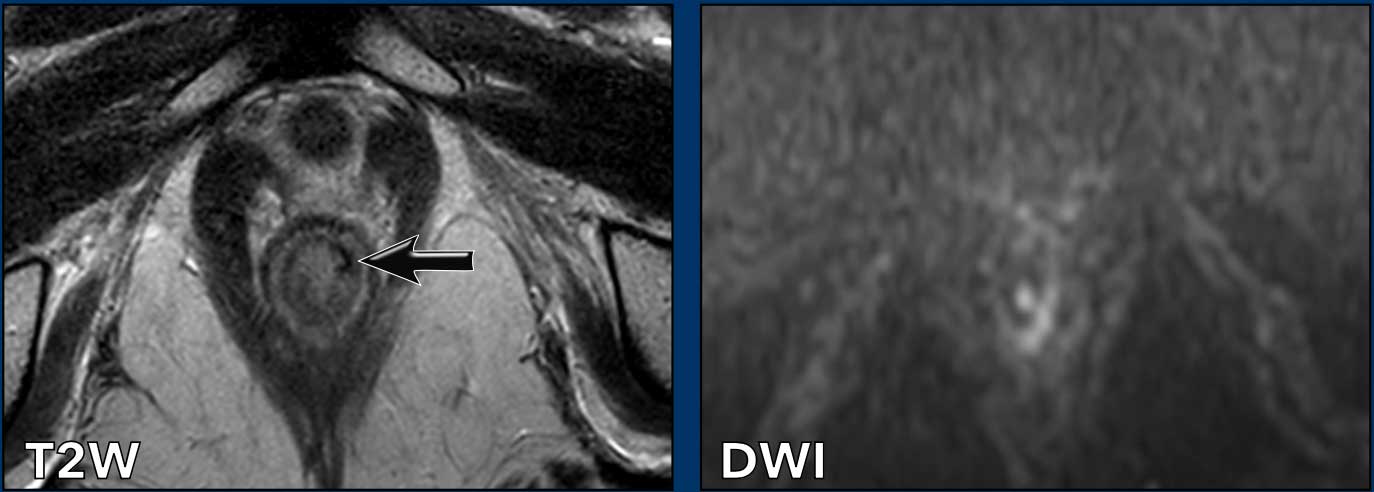

Hình ảnh

Một khối u xâm lấn 2/3 dưới của ống hậu môn.

Khối u xâm lấn cơ thắt trong, khoang liên cơ thắt và cơ thắt ngoài từ khoảng 12 giờ đến 3 giờ.

Không có xâm lấn sàn chậu, trực tràng hoặc bờ hậu môn.

Một ví dụ khác cho thấy khối u xâm lấn ½ trên của ống hậu môn.

Khối u xâm lấn cơ thắt trong, khoang liên cơ thắt và cơ thắt ngoài từ 7-10 giờ.

Khối u xâm lấn cơ mu-trực tràng và cơ nâng hậu môn bên phải (mũi tên) và lan rộng vừa qua mức chỗ nối hậu môn-trực tràng (đường chấm) vào đoạn xa trực tràng.